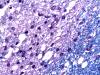

A left frontal lobe biopsy was performed and yield the following representative photomicrographs.

GFAP

M.

On CT scan, there is multiple hypodense white matter lesions that appear to spare a thin layer of subventricular white matter (Panel A). The T2-weighted images on MRI provides a more accurate estimation. The white matter in the occipital lobes is most affected (Panel A). There is extensive vacuolar changes in the white matter (Panel B and C) and there is a questionable increase in cellularity. In some of the thin walled blood vessels, there is a thin layer of perivascular lymphocytic infiltration which is free of atypia (Panel D, E, and F). The lymphocytes do not appear to extends into the parenchyma. On higher magnification, some large reactive astrocytes can be seen (Panel G). In a minority of areas, some concentric rings can be seen on hematoxylin-eosin stained sections (Panel H). These rings appear to be alternating rings of myelinated and demyelinated white matter and the vacuolar changes appear to be limited mainly to the concentric lesions. The adjacent myelinated areas are spared (Panel I). In some areas, the level of myelin loss appears to be proportional to the level of vacuolar changes (Panel J and K). On immunohistochemistry for glial fibrillary acidic protein (GFAP), the degree of gliosis is also more impressive in areas with more prominent vacuolar changes (Panel L and M). The vacuolar areas also appear to have a reduced density of axons (Panel N). Axonal spheroids are also present in these areas (Panel O). Although a prominent infiltration of foamy histiocytes is not noted on hematoxylin-eosin stains, immunohistochemistry for CD68 illustrated positive cells in a minority of demyelinated areas (Panel P). These cells lacks the foamy nature of macrophages and their morphology would suggest microglial cells. The reactive astrocytes are not immunoreactive for CD68 (Panel Q). Immunohistochemistry for T-cells (CD3) and B-cells (CD20) demonstrates only a thin rim of perivascular infiltration without significant extension into the surrounding parenchyma (Panel R, S, and T).